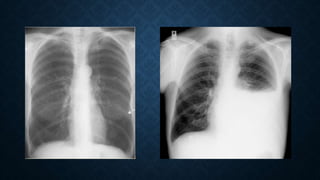

NORMAL CHEST X-RAY (RED) COMPARED TO

RADIOPAQUE (BLUE) AND HYPERTRANSLUSCENT

(GREEN) FILMS